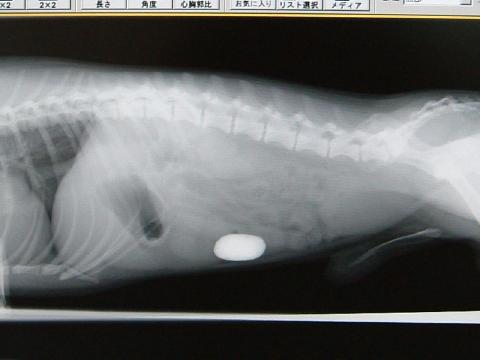

レントゲン検査・・・腸内に卵型の石と思われる異物が確認された

レントゲン写真の位置から小腸内に閉塞している異物(石?)が認められました。血液検査は頻回の嘔吐による脱水と、消化管内の炎症を疑わせる所見でした。